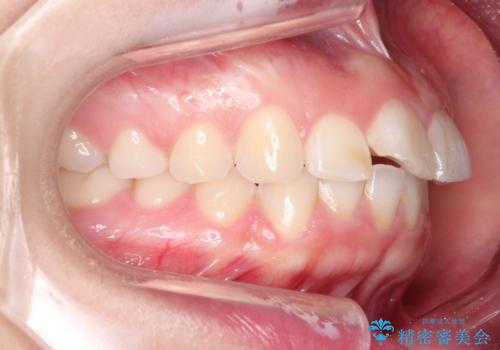

【インビザライン】前歯が出ているのを治したい

- 前歯が出ていることを主訴に来院されました。

前歯の突出感が改善され、満足していただきました。